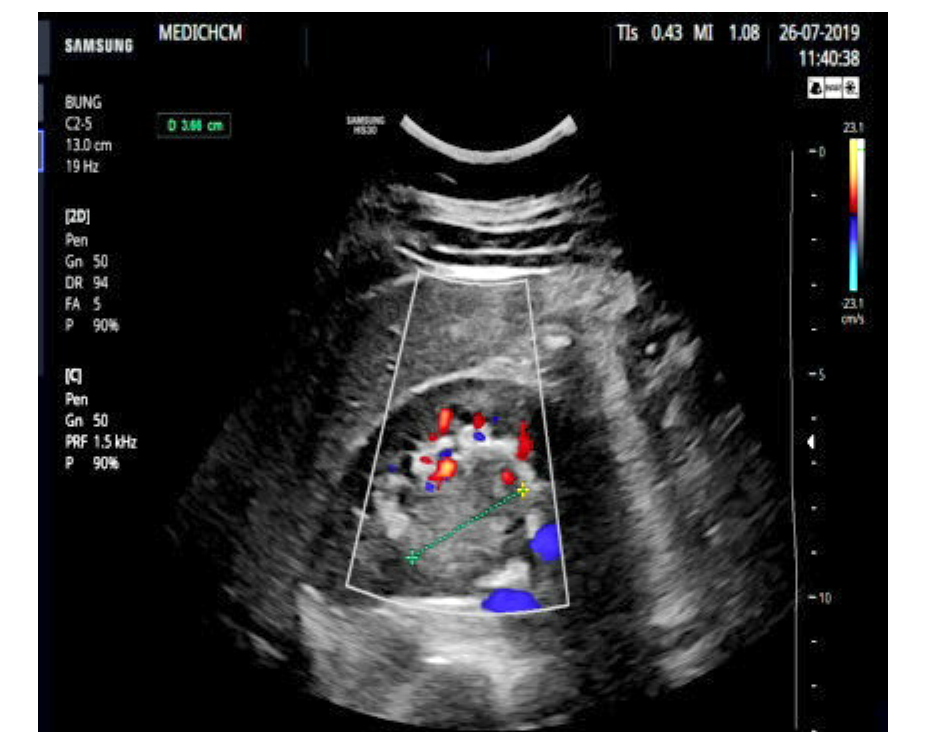

VIETNAMESE MEDIC ULTRASOUND CASE 560 TUMOR IN HORSESHOE KIDNEY, Dr Horseshoe Kidney Tumor — horseshoe kidney is a rare condition where the kidneys fuse together at their base, forming a u or horseshoe. The tumor can localized at any part of the. surgical management of horseshoe kidney tumors is complex, but feasible through both open and minimally invasive surgery after meticulous. horseshoe kidney (hsk) is a common renal fusion anomaly.. Horseshoe Kidney Tumor.

VIETNAMESE MEDIC ULTRASOUND CASE 560 TUMOR IN HORSESHOE KIDNEY, Dr Horseshoe Kidney Tumor surgical management of horseshoe kidney tumors is complex, but feasible through both open and minimally invasive surgery after meticulous. — patients with horseshoe kidneys are at increased risk for upj obstructions, nephrolithiasis, vesicoureteral reflux, urinary tract infections,. — rcc is the most common neoplasm associated with horseshoe kidney. We undertook this study to discuss various anomalies associated.. Horseshoe Kidney Tumor.

VIETNAMESE MEDIC ULTRASOUND CASE 560 TUMOR IN HORSESHOE KIDNEY, Dr Horseshoe Kidney Tumor — horseshoe kidney is a rare condition where the kidneys fuse together at their base, forming a u or horseshoe. surgical management of horseshoe kidney tumors is complex, but feasible through both open and minimally invasive surgery after meticulous. The tumor can localized at any part of the. — patients with horseshoe kidneys are at increased risk. Horseshoe Kidney Tumor.

VIETNAMESE MEDIC ULTRASOUND CASE 560 TUMOR IN HORSESHOE KIDNEY, Dr Horseshoe Kidney Tumor We undertook this study to discuss various anomalies associated. — horseshoe kidney is a rare condition where the kidneys fuse together at their base, forming a u or horseshoe. The tumor can localized at any part of the. — rcc is the most common neoplasm associated with horseshoe kidney. surgical management of horseshoe kidney tumors is complex,. Horseshoe Kidney Tumor.